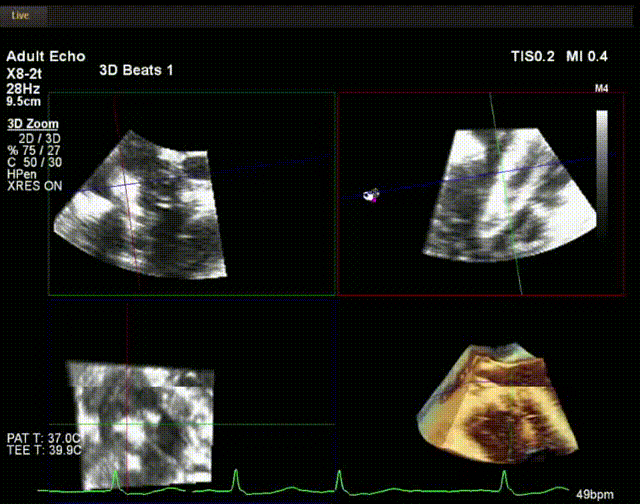

術中超聲

陸方林教授通過遠程線上帶教的方式,與林逸賢教授團隊共同完成了此次LuX-Valve Plus人工瓣膜的首例植入。術后食道超聲提示三尖瓣反流完全消失,無瓣周漏,且LuX-Valve Plus人工瓣膜的兩個夾持鍵成功抓取瓣葉,錨定牢固,人工瓣膜穩定性良好。